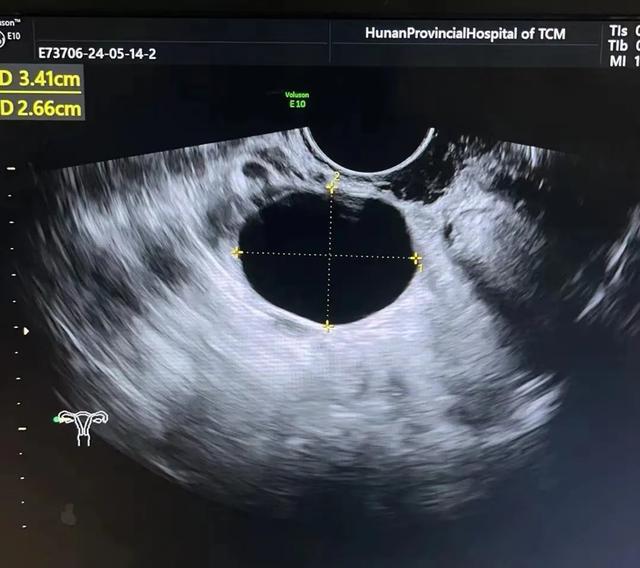

1、滤泡囊肿及卵泡囊肿:

①子宫一侧可见单纯性、无回声囊肿,内壁光滑,一般<2.0cm,最大可达10.0cm,动态观察囊肿变小或消失。

②包膜完整,壁薄,呈类圆形,伴后方回声增强。

③囊肿周边有时可见正常卵巢组织。

④囊肿周边可测到血流信号。

⑤一般经过1-3个月经周期后,最长者数月后囊肿自然消失。